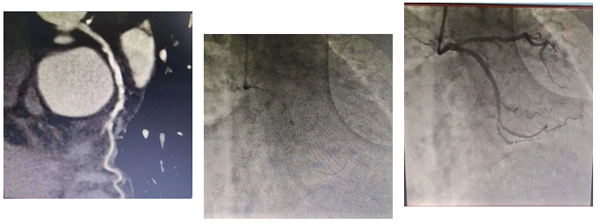

患者为78岁女性,主因间断胸闷3年就诊,冠状动脉CTA提示冠状动脉严重钙化,左主干管壁多发钙化,管腔狭窄,前降支严重钙化伴管腔狭窄大于70%,回旋支严重钙化伴有管腔严重狭窄。由于钙化严重,术前刘巍主任团队就做好了充分的准备。冠状动脉造影提示左前降支严重钙化伴有多发斑块管腔偏细,回旋支远段85%狭窄,右冠状动脉全程钙化伴有多发斑块。计划使用IVUS对回旋支狭窄进行评估,但IVUS无法通过近段病变,IVUS提示近段钙化角度大于270°。刘巍主任使用1.25mm磨头对回旋支进行旋磨,旋磨后,球囊及IVUS可顺利通过钙化病变到达远端,IVUS提示管腔弥漫性斑块,斑块负荷重,远段管腔严重狭窄,刘巍主任决定植入支架,经旋磨后,支架可顺利通过钙化病变部位,成功释放,支架膨胀效果良好。术后患者胸闷明显缓解。

冠脉CTA显示LCX狭窄伴钙化,对LCX进行旋磨术后LCX血管狭窄明显改善